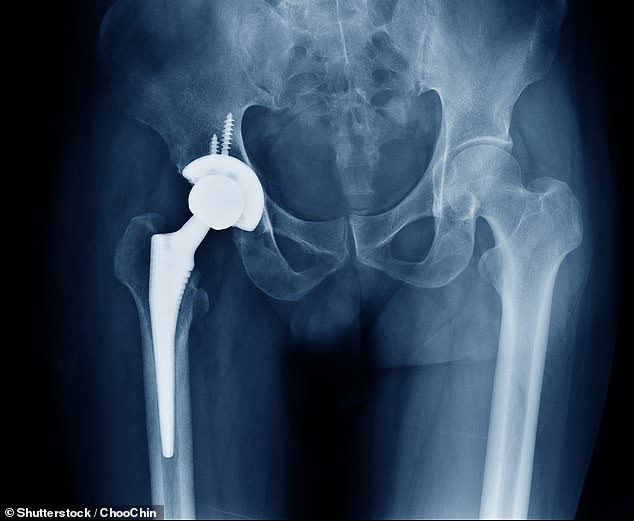

The affected products include 15 different bone cement variants, some of which are standard fixation cements used in hip and knee replacements. These cements act like a strong grout, filling the space between the metal implant and the patient's bone to create a stable bond. Others contain antibiotics, used in cases of high infection risk or during revision surgeries, where a previous joint replacement has failed or become infected. Some products are specifically designed for infection management, creating temporary cement 'spacers' in two-stage revision procedures.